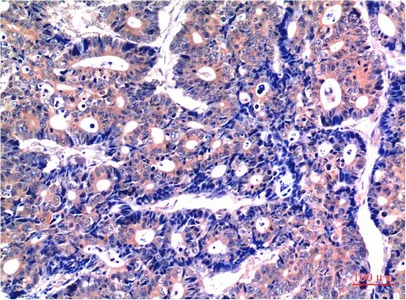

GSK3 beta Mouse Monoclonal Antibody

Cat: AMM03710

GSK3 beta (9F9) Mouse Monoclonal Antibody

Cat: AMM03603

GSK3 beta (9B1) Mouse Monoclonal Antibody

Cat: AMM03604

GSK3 beta (4C4) Mouse Monoclonal Antibody

Cat: AMM03605